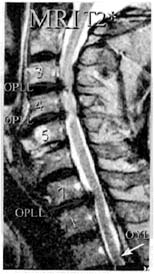

頚椎後縦靭帯骨化症 1 頚椎後縦靭帯骨化症とは 頚椎椎体の後方に存在する後縦靱帯が骨化し 現在のところ原因不明 脊髄を圧迫するために頚髄の症状が起こります 2 症状 症状としては頚椎症性脊髄症と同じです 頸椎症性脊髄症のページ 3